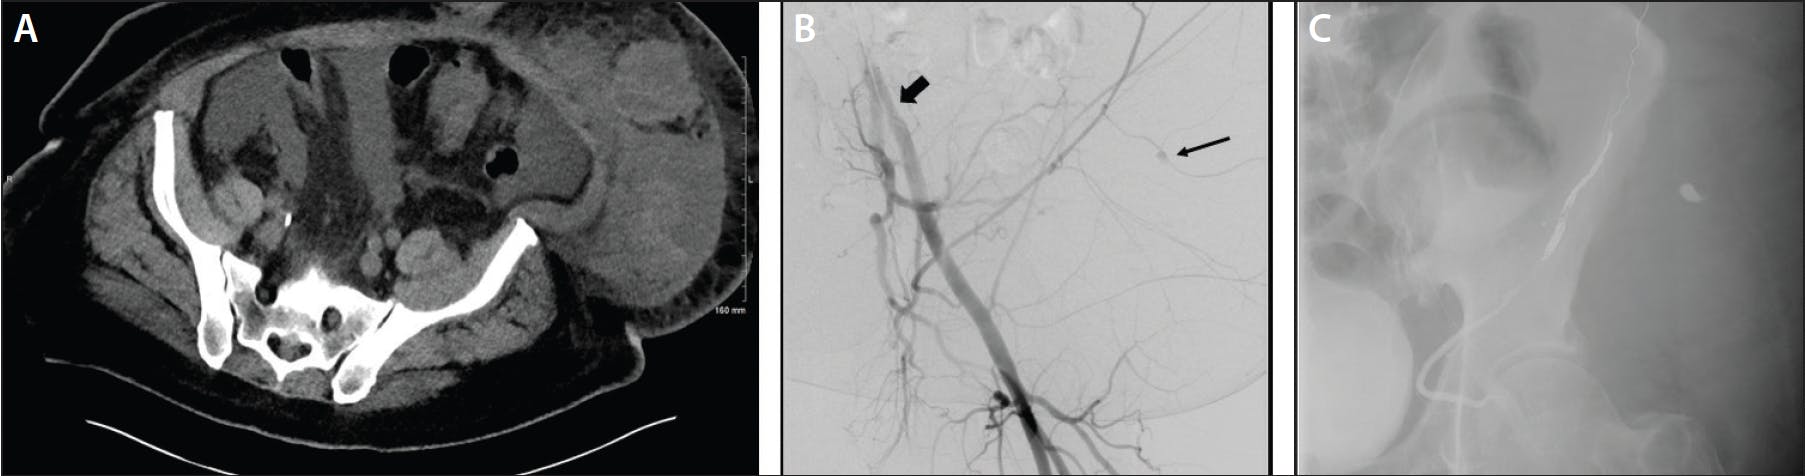

Figure 2. A man in his early 50s with metastatic salivary gland carcinoma (ex pleomorphic adenoma) was transferred from an outside facility for management of a ruptured hepatic metastasis. Hemoglobin dropped to 6.8 from 8.5 g after 2 units of PRBC. CTA performed with a large, ruptured segment 7 mass noted high-density material compatible with recent hemorrhage but no active arterial extravasation (A). DSA via right radial access with a 5-F Sarah catheter (wide arrow) seated in the superior mesenteric artery, demonstrating replaced right hepatic artery (B). Selective 2.8-F microcatheterization of the posterior branch of the right hepatic artery with multiple masses and opacification of ruptured segment 7 lesion noted (arrows) (C). Superselective microcatheterization of the segment 7 branch (arrow) supplying the mass, embolized with 250-µm beads (D). The patient responded well, with no further transfusion requirements.